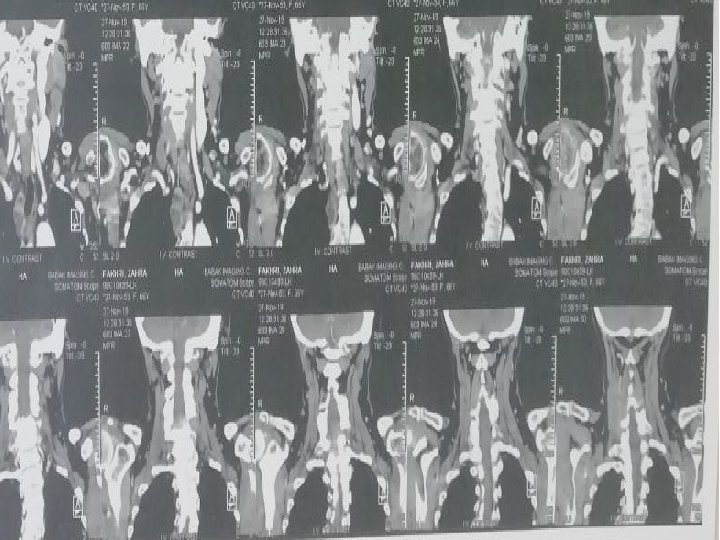

CT Scan axial of neck with and without IV Contrast 98/6/9